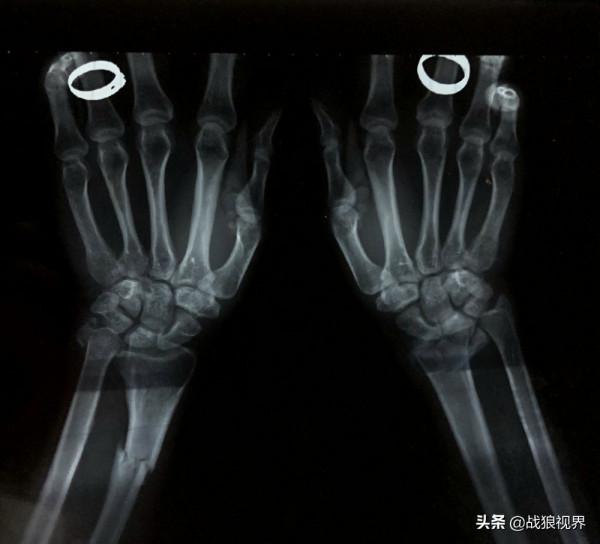

禍不單行。2015年12月28日,為給擺攤位架設電線,黎爸爸不小心從二十米高滑梯摔下,致使雙手骨折。這一摔不單額外花去一大筆治療費,還讓黎啟均的手如殘疾一樣,不再像以前一般靈活,生意也慢慢冷清下來。

病情反覆的揪心、生活的艱難,讓夫妻倆摩擦不斷,感情慢慢耗盡,直至走到了婚姻的盡頭。(圖為:黎啟均意外摔下,致使雙手骨折診斷報告)為他手腳麻利,攤位還能維持基本生計。兒子生病後,為了快攢點錢給兒子手術,黎爸爸與時間賽跑,打算晚上也出門擺攤。(圖為:黎啟均意外摔下,致使雙手骨折診斷報告)